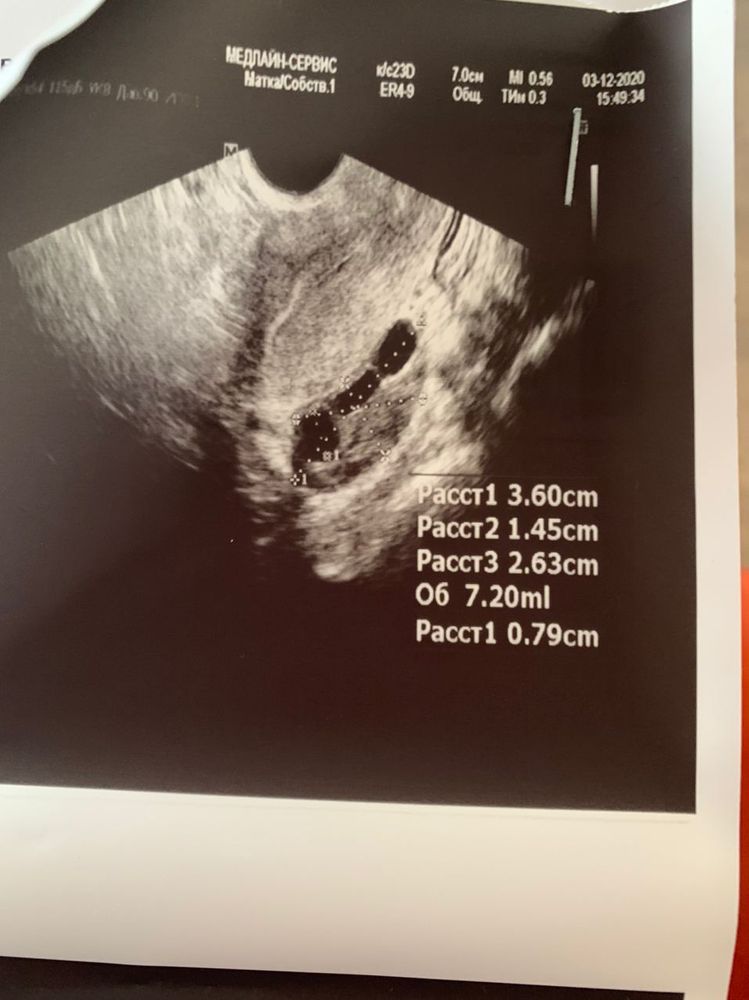

Пошла сегодня на фолликулометрию с полной уверенностью, что овуляция будет вот вот. А тут оказывается, у меня даже доминантного фолликула ни в одном яичнике нет.

У меня еще МФЯ, вот не знаю, есть шанс, что в этом цикле еще что-то будет или уже не на что надеяться?